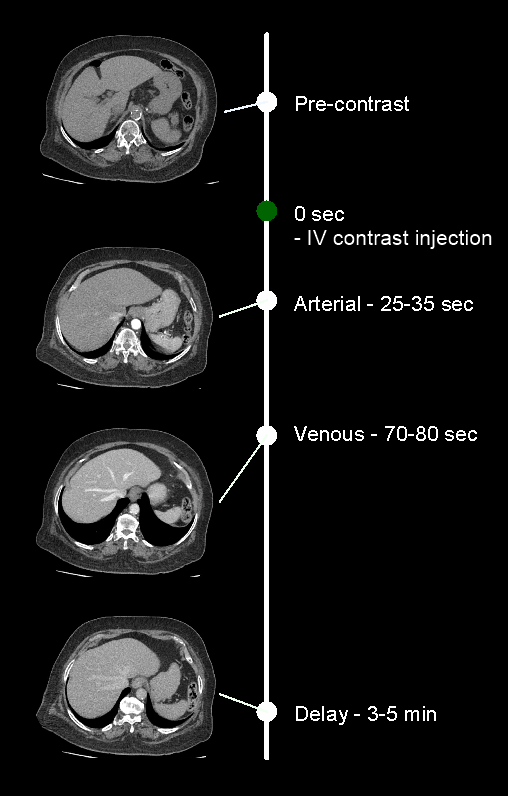

- There are generally 4 phases in this scan.

- Plan pre-contrast scan to cover from the dome of the diaphragm to a level just below the ischial tuberosities.

- Plan arterial and delayed phases to cover form the Dome of the diaphragm to the upper margin of the sacroiliac joints.

- Plan portal-venous phase to cover form the Dome of the diaphragm to a level just below the ischial tuberosities.

- Set the phase initiation.

Explanation: either triggering or timing method can be used to initiate phases on time.

a. Bolus tracking method

Scan-and-view slice (S and V) is placed just above the diaphragm, and threshold value is setto 180, and triggering ROI is placed in the descending aorta. Keep a ten seconds gap between the contrast initiation point and triggering point. Either automatic or manual triggering can be used. Refer thoracic aortogram article for more details.